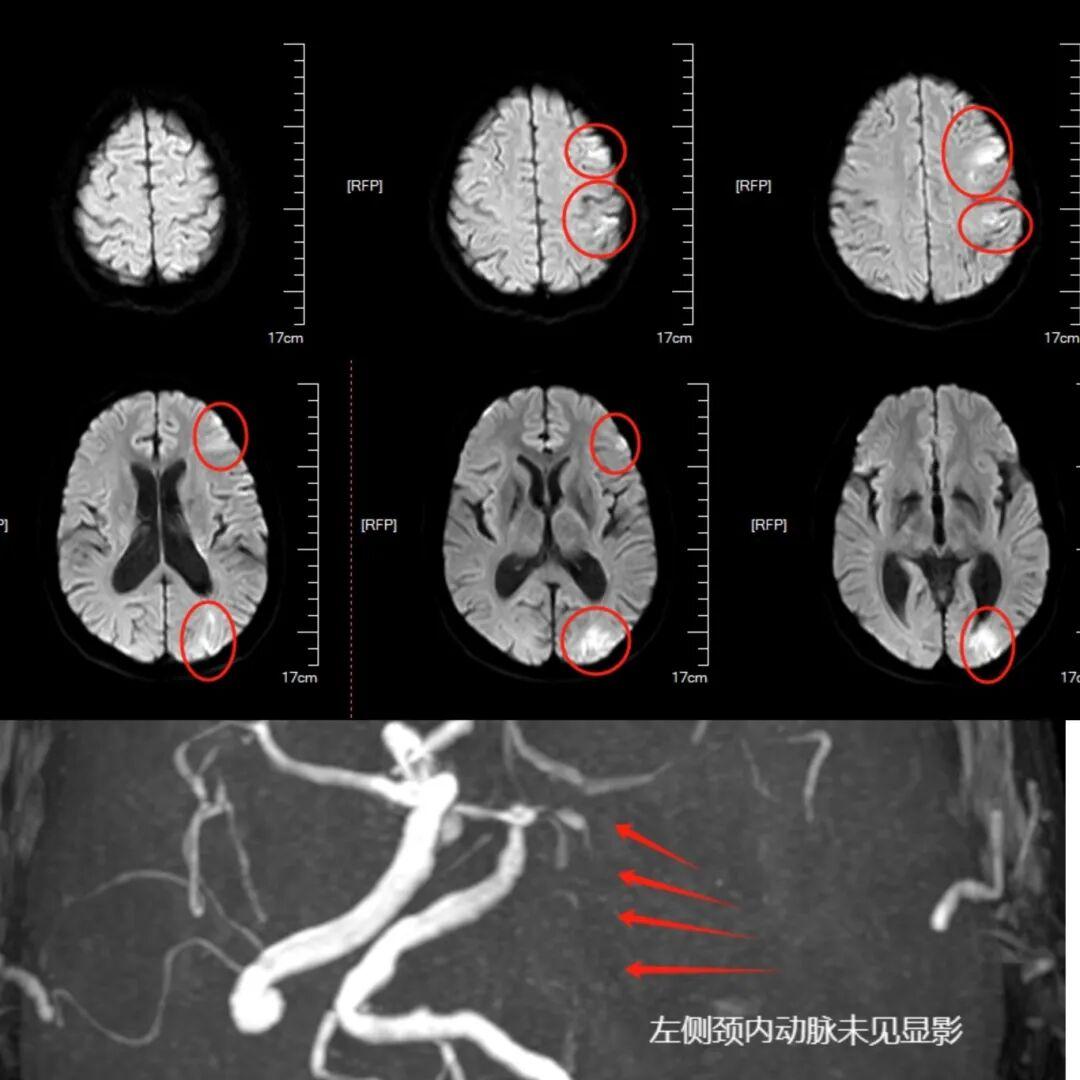

入院时,薛先生嗜睡、混合性失语,右侧肢体力0级,NIHSS评分达18分,病情危急。因患者孤身、家属远在外地,医院立即开通卒中绿色通道,急诊团队迅速完成颅脑CT排除脑出血。鉴于发病时间不明无法静脉溶栓,结合症状神经内科医生高度怀疑颅内大血管闭塞,后续磁共振证实其左侧颈内动脉末端急性闭塞,大脑面临严重缺血危机。

医院神经内科介入团队评估后,决定立即实施介入取栓手术。在征得家属电话同意并启动应急签字程序后,团队于全麻下通过微创方式,抽吸并以支架“网”出栓子,成功开通闭塞血管,为患者抢回“大脑生机”。